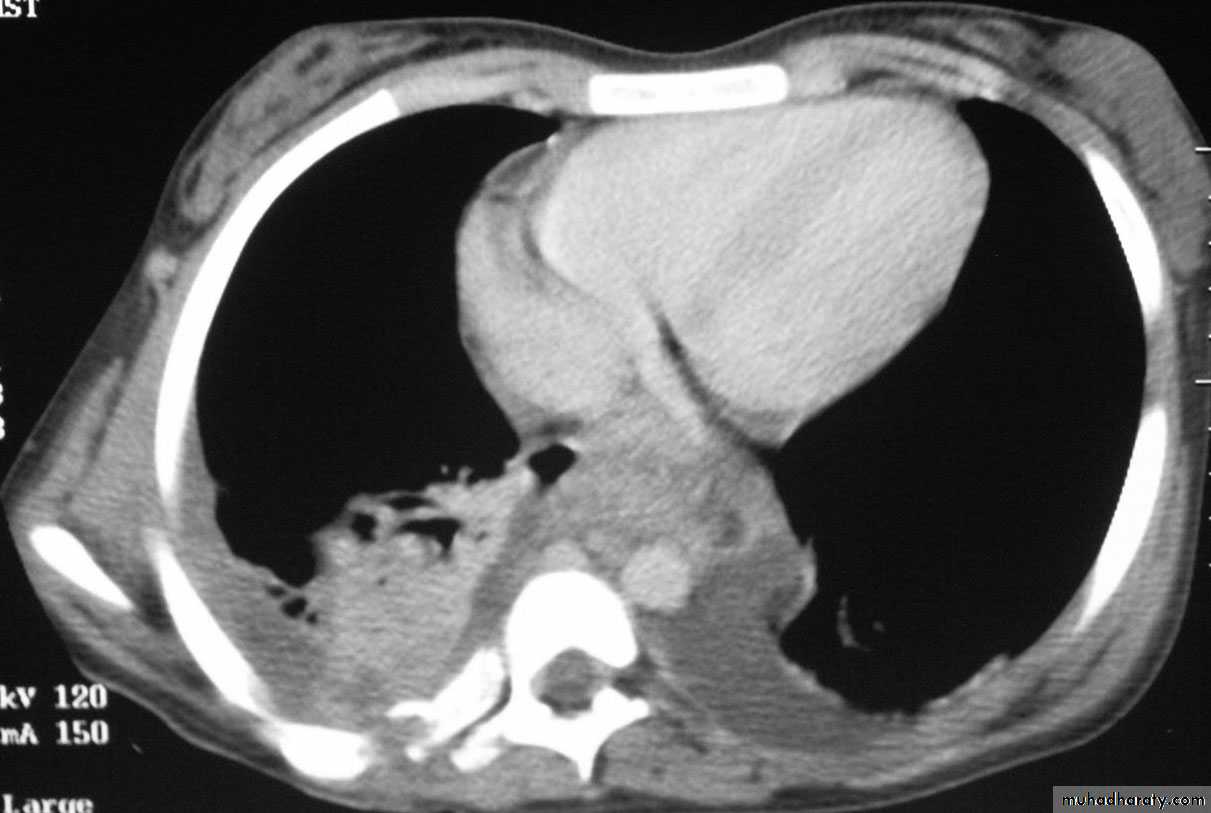

Chest CT scan shows multiple round nodules and masses of varying sizes in both lungs, consistent with metastases. There are also small bilateral pleural effusions.

Multiple and bilateral secondaries

Computed tomography scan showing nodular thickening of interlobular septa (white arrow), seen as polygonal arcades with thickened and nodular limbs, and ground-glass opacities (black arrows).